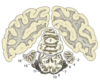

Label the diagram

Label the diagram (MAJOR STRUCTURES ONLY!)